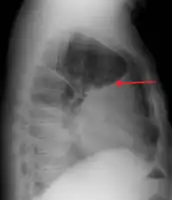

A pleural effusion as seen on lateral upright chest x ray- Pleural effusion as seen behind the heart.[13]